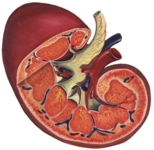

Hasarlı Böbreklerin İyileşme Şansı Nedir?Böbrekler, vücudun sıvı dengesini sağlamada, atık maddeleri filtrelemede ve elektrolit dengesini düzenlemede kritik bir rol oynayan önemli organlardır. Hasar görmüş böbreklerin iyileşme şansı, hasarın türüne, derecesine ve hastanın genel sağlık durumuna bağlıdır. Bu makalede, hasarlı böbreklerin iyileşme süreci, etken faktörler ve tedavi yöntemleri ele alınacaktır. Böbrek Hasarının Nedenleri Böbrek hasarının birçok nedeni bulunmaktadır. Bu nedenler genel olarak şu şekilde sıralanabilir:

Böbrek Hasarının Dereceleri Böbrek hasarının dereceleri, bu organların işlevselliğini etkileyen faktörler arasında önemli bir yer tutar. Hasar genellikle üç ana dereceye ayrılabilir:

İyileşme Süreci ve Faktörler Hasarlı böbreklerin iyileşme süreci, birçok faktöre bağlıdır:

Tedavi Yöntemleri Hasarlı böbreklerin tedavisinde kullanılan yöntemler, hasarın türüne ve derecesine bağlı olarak değişkenlik gösterir. Bazı yaygın tedavi yöntemleri şunlardır:

Sonuç Hasarlı böbreklerin iyileşme şansı, hasarın türüne, hastanın genel sağlık durumu ve tedaviye yanıtına bağlı olarak değişiklik göstermektedir. Erken teşhis ve uygun tedavi yöntemleri ile iyileşme olasılığı artırılabilir. Bu nedenle, böbrek sağlığını korumak için düzenli kontroller ve sağlıklı yaşam tarzı benimsemek önem arz etmektedir. Ekstra Bilgiler Böbrek sağlığını korumak için aşağıdaki önerilere dikkat edilmesi önemlidir: